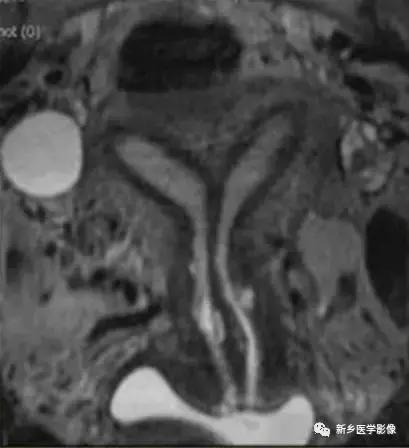

完全型纵隔子宫:宫底平坦,纵隔贯穿宫腔和宫颈

不完全型纵隔子宫:宫底平坦,纵隔未达宫颈内口水平